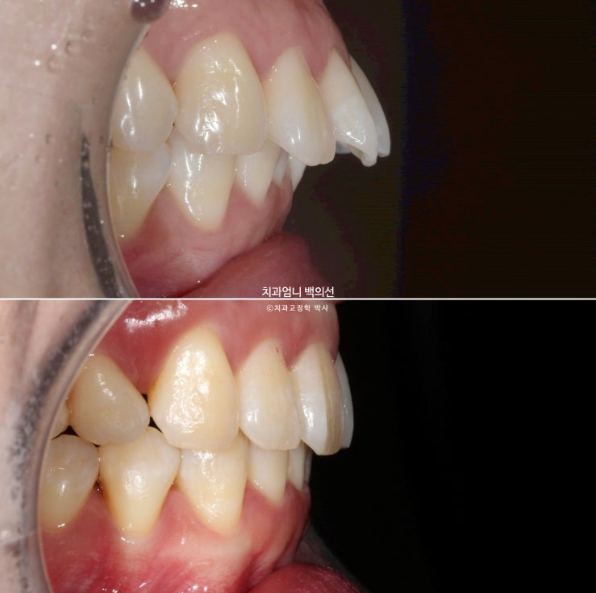

치료시작 8개월차 발치공간으로 앞니가 이동하면서 원래 깊었던 앞니 교합이 점점 더 깊어지는 것이 관찰됩니다.

이 부분 해결을 위해서는 원래 계획에 없었지만 앞니에 미니스크류 2개를 추가로 식립하고 고무줄을 걸기 시작합니다.

23년 3월부터 24년 5월까지 1년 2개월간 52개의 장치를 낀 후 재제작 당시의 모습 보여드리겠습니다.

과개교합은 잘 개선이 되었습니다.

발치공간이 아직 남아있고 앞니 각도의 개선이 더 필요합니다.

한달간 추가장치 제작기간을 기다려 24년 6월부터 두번째 세트의 장치를 끼기 시작했습니다.

25년 1월까지 7개월간 추가장치를 끼고 치료가 마무리 되었습니다.